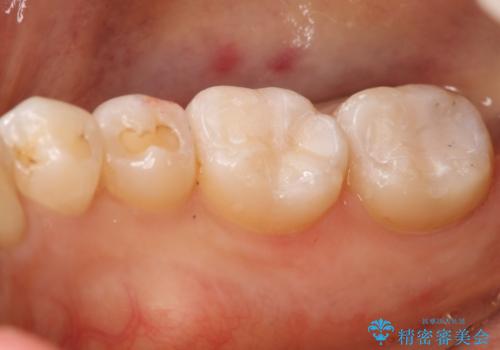

奥歯を綺麗にしたい

- 右下6・7番の咬合面に詰められた保険材料が劣化していたので、審美性・切削量を考慮しセラミックインレー治療を選択しました。

- 154000円(2本分)費用は治療当時の料金となります

劣化した保険材料・虫歯を全て除去した上で形成しています。